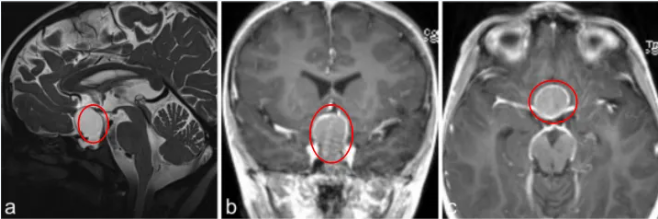

一份诊断书将整个家庭置于重大抉择关口——颅咽管瘤。该诊断带来巨大冲击。垂体作为深藏于大脑底部、承担内分泌调控中枢职能的微小器官,一旦遭受损伤,意味着儿童的生长、发育乃至日常生命活动均可能失去支持。值得庆幸的是,他们并未长时间沉溺于无助情绪,而是迅速开启了康复历程。

此诊断结果带来巨大冲击,令小宇家人深感无助。他们了解到颅咽管瘤解剖位置特殊,手术操作难度极高,轻微不慎即可能损伤周边神经与组织,为孩子遗留终身功能障碍。怀揣最终希望,小宇家人带领他寻访施罗德教授。施罗德教授明确指出,尽管小宇的手术难度较高,但通过神经内镜微创手术技术,有望实现肿瘤完全切除,结合术后规范的激素替代治疗,患儿有望逐步恢复,重返正常生长发育进程。

经充分沟通并取得家长信任后,施罗德教授带领医疗团队制定了个体化手术方案。手术当日,施罗德教授借助神经内镜技术精准定位肿瘤位置,实施肿瘤的精细剥离,全程规避关键神经与组织,最终顺利完成肿瘤全切手术,整个手术过程平稳,术后小宇迅速脱离危险状态。